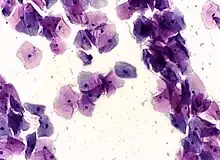

In the conventional Pap smear, the collected cells are smeared on a microscope slide, and a fixative is applied. The slide is evaluated in a pathology lab to identify cellular abnormalities.